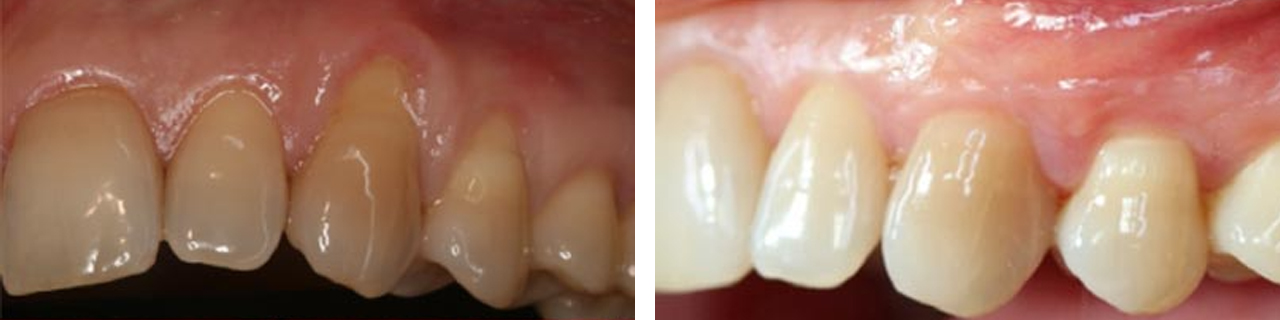

Raíces expuestas

Cubrimiento de raíces expuestas y aumento del grosor de la encía.